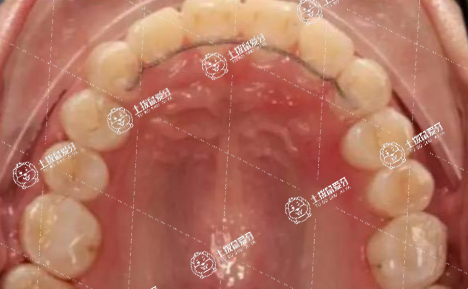

矯正牙齒牙齦腫了是怎么回事

牙齒矯正導(dǎo)致牙齦腫痛可能是正常的生理現(xiàn)象,也可能是病理性因素所致,一般需要根據(jù)具體情況進(jìn)行具體分析。

通過口腔X光片檢查,判斷牙齦腫痛的原因,如果只是輕微紅腫,并不存在發(fā)炎,通常屬于牙齒矯正期間正常的反應(yīng),如果疼痛比較嚴(yán)重,也可以遵醫(yī)囑服用些止痛的藥物,或是通過調(diào)整牙齒矯正的力度來改善。